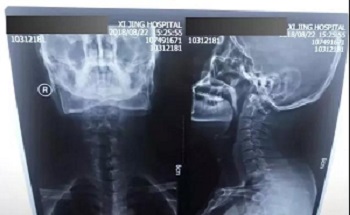

十二、拍摄时,尽可能的将片子上的文字信息拍摄清楚,并将左右拍摄清楚(片子上有标R,表示右侧right,L, 表示左侧left的意思), 每张片子上的文字都能按照阅读习惯拍正确,不要拍反了。

拍摄时,必须要对着片子上的文字对焦, 方向正确,将文字拍摄得清晰可视,保证放大图片后文字依然清晰可见(如下图),尽可能多的保留片子上的信息。